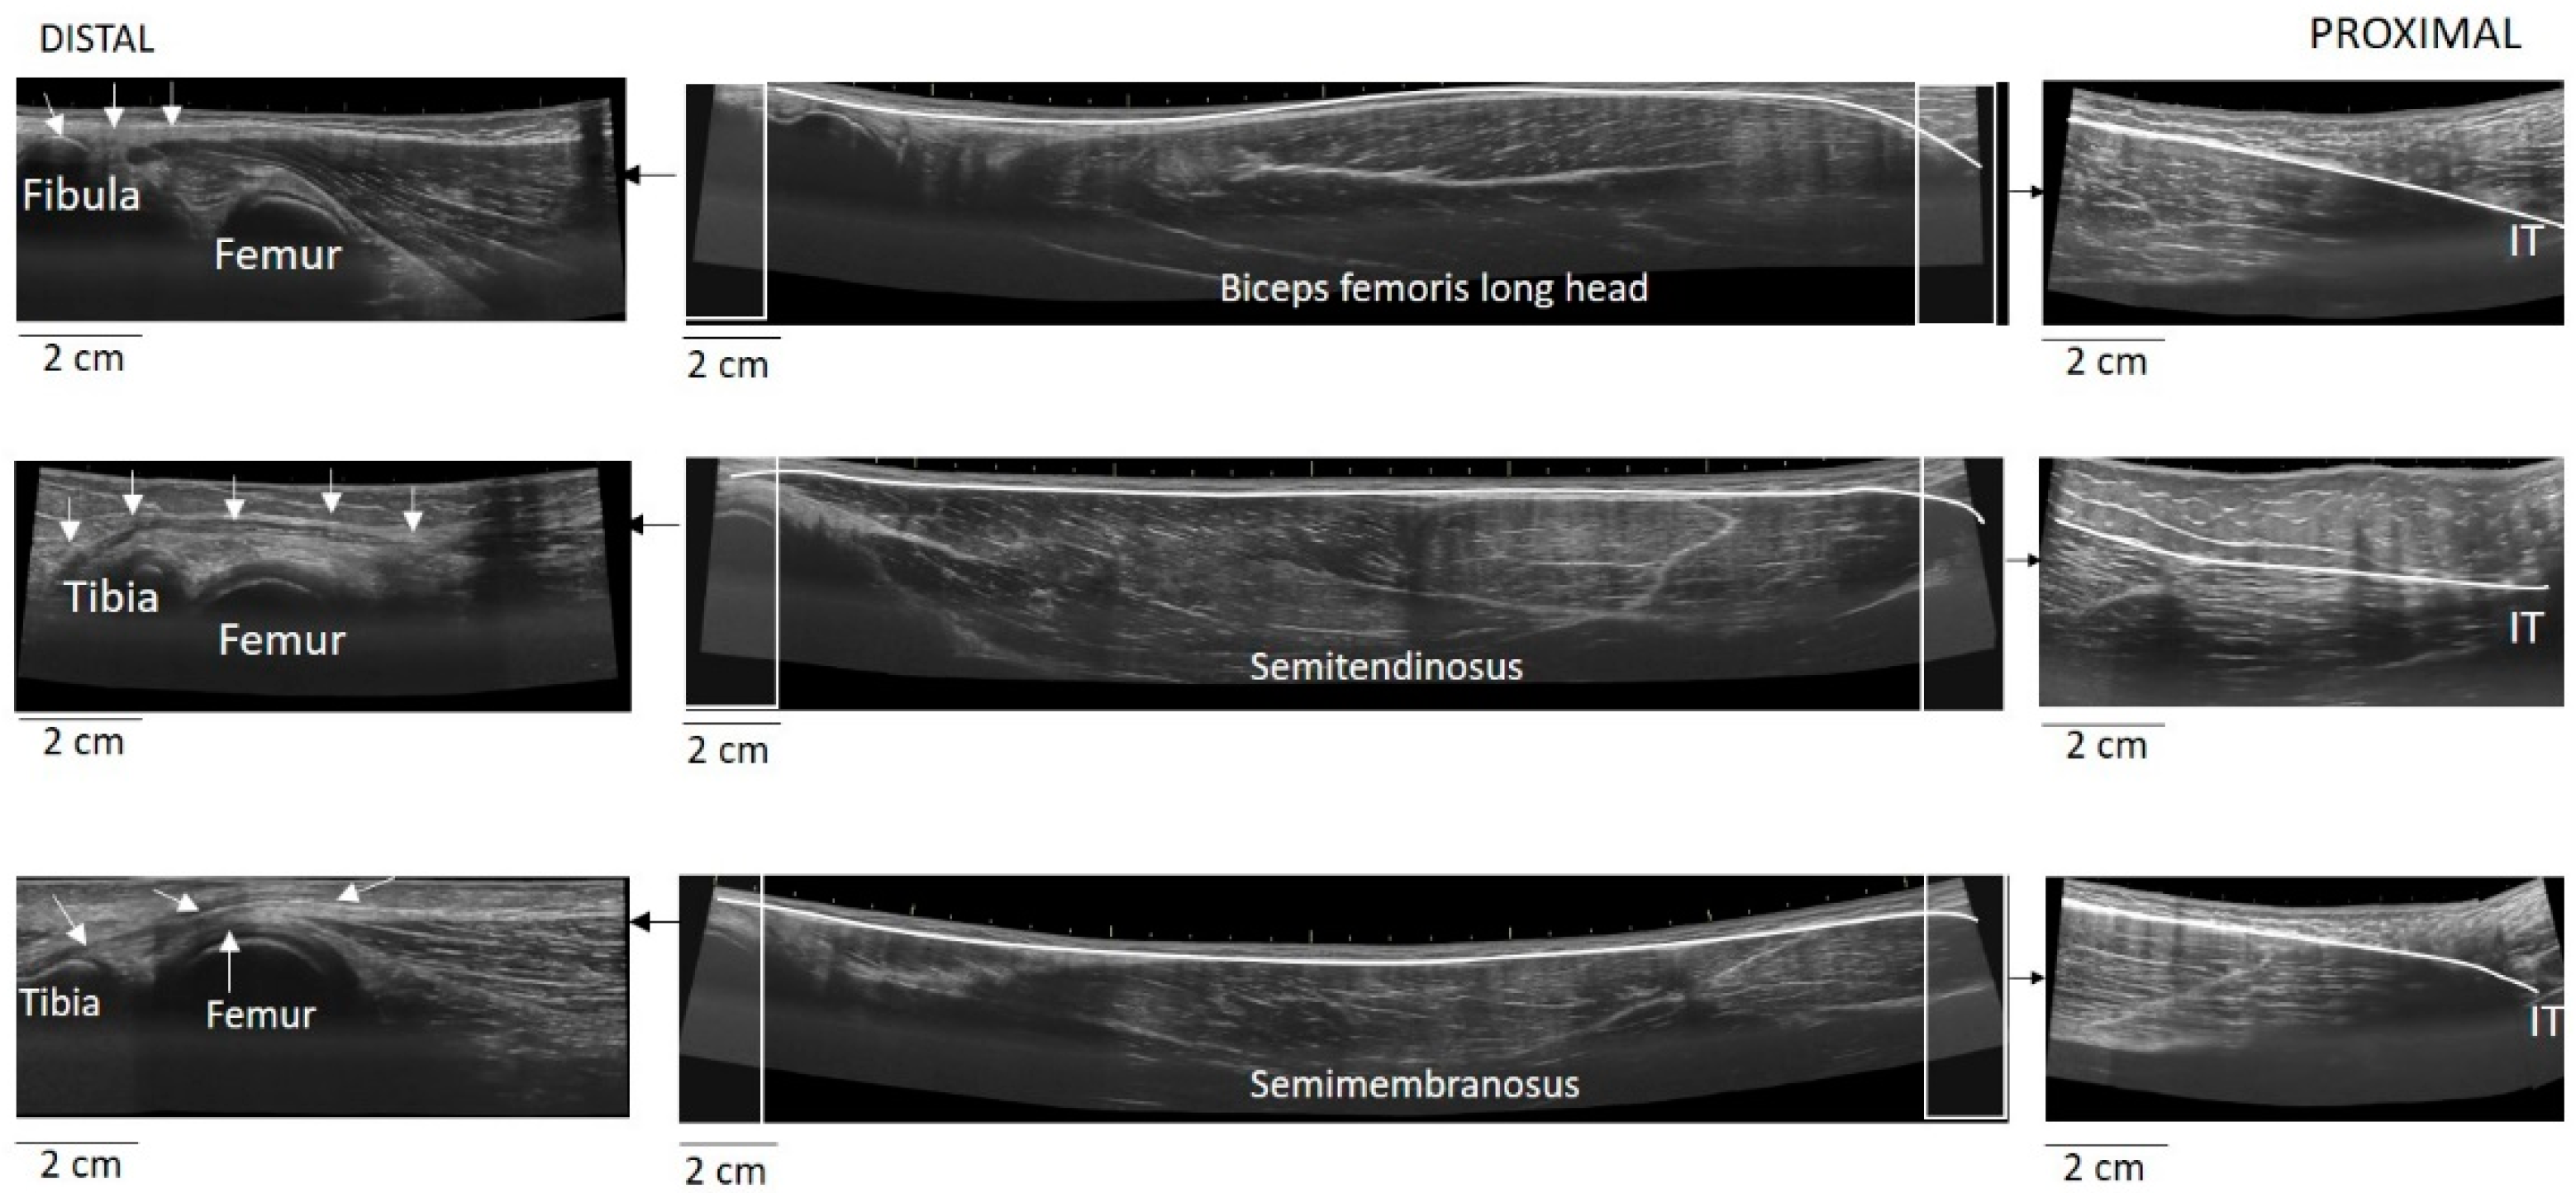

The EFOV protocol included continuous scanning of the whole LMTU from the distal to proximal end (Figure 3). In each testing position, the US probe was slowly and continuously moved from the most proximal to the most distal aspect of each muscle. The probe was moved perpendicularly to the skin. To achieve better and consistent images, each muscle was scanned and the path of the probe that best identified the underlying muscle was marked on the skin. Subsequently, each MTU was scanned until three scans with acceptable image quality (i.e., a clear, continuous depiction of the superficial and deep aponeurosis without any sudden changes in the image across the muscle) were obtained. On several occasions, the distal and proximal tendons could not be visualised using a single long scan due to uneven surface anatomy. In these cases, we used an echo-absorptive marker on the skin and additional EFOV scans of these muscle segments were taken. The long free tendon of the ST from the medial aspect of the tibia to the fascia cruris was evaluated only with the hip in neutral position and the knee at 45° of the flexion, as due to curvature of the tendon along the femur and the tibia, complete visualisation of its path at all combinations of hip and joint movement was difficult. Great care was taken to ensure that consistent minimal pressure was applied with the probe to avoid compression of the muscle. Furthermore, a generous amount of water-soluble transmission gel was applied to the skin, to enhance acoustic coupling and reduce near-field artifacts. GE Logiq LogicView software was used to produce panoramic images of each MTU in real time. The US EFOV images were digitally stored and analysed using ImageJ Software (Version 1.47v, National Institutes of Healt, Bethesda, MD, USA). In each image, the segmented line tool was used to digitise the LMTU from the most proximal to most distal end of the superficial aponeurosis (Figure 3). In cases where more than one scan was used to visualise the same muscle, the final LMTU was estimated by adding the lengths of the muscle in each respective scan.

Figure 3. Measurement of muscle-tendon unit using EFOV-US technique. In each panel of images, the center image presents each muscle-tendon unit, scanned from the distal to proximal end. To better illustrate the identification of the attachments, zoomed EFOV-US images of the distal (left side) and proximal (right side) are also included. White arrows illustrate the path of each distal tendon. Using the segmented line tool of the ImageJ software, the superficial aponeurosis was digitised and the total line length was considered as the muscle-tendon unit (IT = ischial tuberosity).